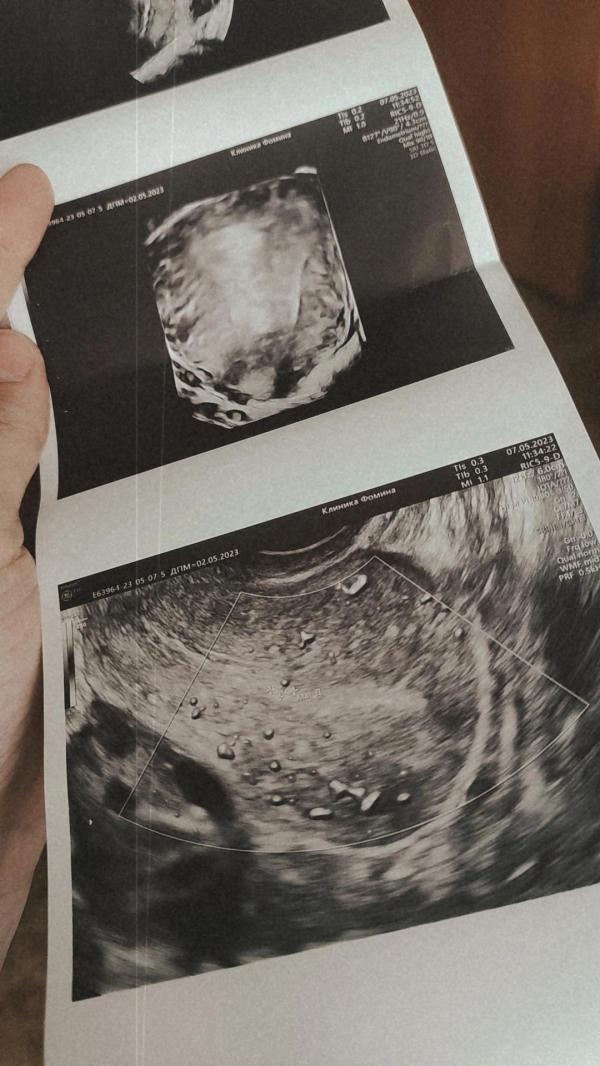

День менструального цикла: 6й день

М - Эхо толщиной, мм: 22

Нашли Эхографические признаки патологии эндометрия (полипы)

М - Эхо размер толщиной, мм : 4.0